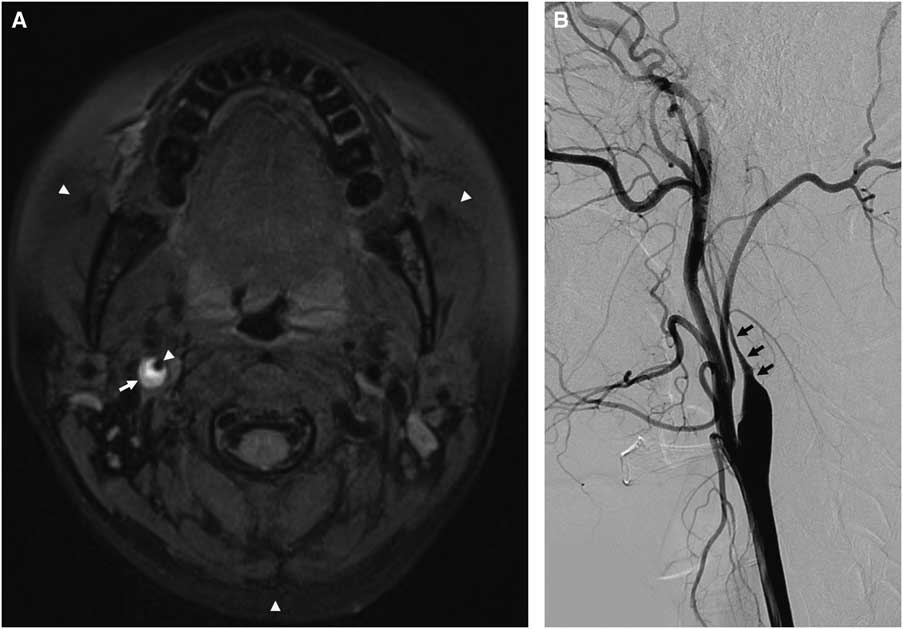

A 34-year-old healthy woman with transient left-side weakness and right-side blurred vision underwent radiologic evaluation. She had a history of minor head trauma during swimming 2 weeks before symptom onset. Initial fat-saturated T1-weighted DANTE-SPACE revealed bright mural hematoma signal (arrow) in the right internal carotid artery, suggestive of artery dissection. The excellent cancellation of blood-flow signal in the carotid lumen concomitant with consistent fat suppression (arrow heads) in the cervical region enabled clear depiction of CAD (Figure 1A). TFCA showed a tapered long segmental stenosis (arrows), which is a typical appearance of proximal carotid artery dissection (Figure 1B). The patient showed good clinical recovery and was subsequently discharged after 7 days. Follow-up MRI taken at 10 weeks after onset depicted resolution of the CAD (arrow) (Figure 2). In this case, non-invasive visualization of a dynamic change of CAD using DANTE-SPACE obviated the need for follow-up TFCA.

Figure 1 Precontrast T1-weighted DANTE-SPACE MRI revealed eccentric bright signal in right proximal carotid artery, suggestive of carotid dissection (A). Catheter angiography showed typical tapering appearance of proximal ICA, suggestive of carotid dissection (B).